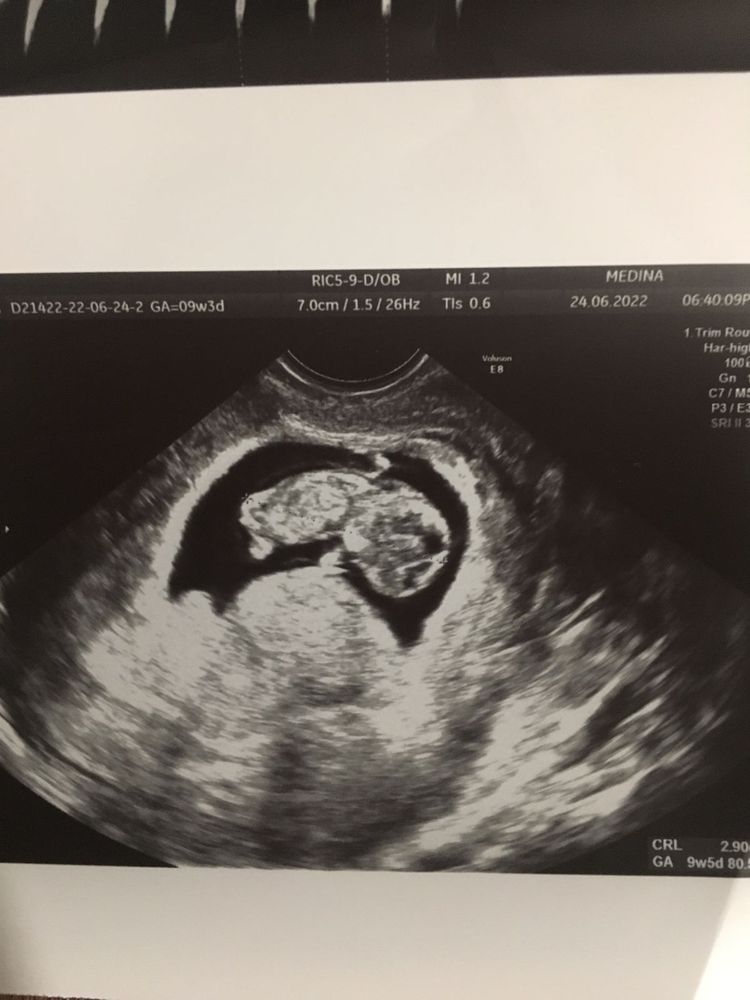

Узи на 9 +3 неделе

У меня вот при третьей беременности после каждого УЗИ мощнейший тонус возникал, аж больно идти было. Потом потихоньку отпускало. И в первом триместре как раз так и было деформировано, узистка сказала, что из-за тонуса это

Лисичка, да вот меня, что и смутило- говоря, что тонуса нет, всё хорошо, написать, что деформировано. Значит, все-таки что-то не так...

Татьяна, значит возможно всё-таки был небольшой тонус. Ничего страшного)